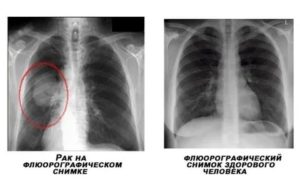

Рак при рентгенографии или рентгеноскопии выглядит как «плюс-ткань» — выраженное затемнение участка лёгочного поля.

Контуры нечёткие, размытые, так как рак растёт во все стороны и затрагивает здоровые ткани. Наличие округлых теней может свидетельствовать об отсеве метастазов.